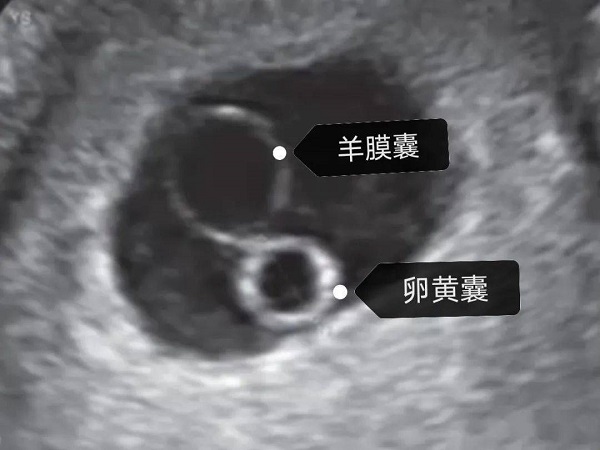

女性怀孕是一个非常复杂且辛苦的过程,为了进一步了解胚胎的生长发育情况,孕期都是需要进行B超检查的。一般来说,在女性怀孕5周左右的时候就能够看到胎心搏动和胎芽了。随着胚胎的逐渐发育,卵黄囊也会逐渐出现,并且会逐渐变大直到胎盘开始发育,才会逐渐消失。不同的孕周卵黄囊和胚芽的大小其实都是不同的,都有一个正常的范围值,具体的大家可以参照一下卵黄囊及胚芽孕周对照表。

卵黄囊及胚芽孕周对照表

在怀孕之后女性都是需要定期到医院进行产检的,尤其是在怀孕初期的时候是需要通过B超检查了解胚胎是否成功着床的。通常情况下,在B超检查报告单中可见看卵黄囊及胚芽的话,那么就表示胚胎是在正常的生长发育的,大多数情况下在女性停经大概7周左右就能够通过B超看到。

当然随着孕周的逐渐增长,卵黄囊和胚芽的大小也是会发生变化的,不同的孕周都是有不同的正常范围的,大家可以参照一下卵黄囊及胚芽孕周对照表来查看是否正常,具体如下:

| 孕周 | 卵黄囊大小 | 胚芽大小 |

| 4周 | 孕囊0.3cm | 孕囊体积很小,B超一般看不清怀孕迹象 |

| 5周 | 孕囊0.4cm | B超可看见小胎囊,胎囊约占宫腔不到1/4,或见胎芽 |

| 6周 | 孕囊0.85cm | B超孕囊清晰可见并且出现了明显的胎芽及胎心跳 |

| 7周 | 孕囊1.33cm | B超可清楚看到胎芽及胎心,胎囊约占宫腔的l/3 |

| 8周 | 孕囊1.66cm46-50岁 | B超可见孕囊约占官腔1/2,胎儿形态及胎动清楚可见,并可看见卵黄囊 |

| 9周 | 孕囊2.15cm | B超可见孕囊几乎占满宫腔,胎盘开始出现 |

| 10周 | 胎儿2.83cm | B超可见孕囊开始消失,胎盘可见,胎儿活跃在羊水中 |

| 11周 | 胎儿3.62cm | B超可见孕囊完全消失,胎盘清晰可见 |

由此可见,女性怀孕期间卵黄囊和胚芽也并不是一直都存在的,一般在胎盘形成之后卵黄囊和胚芽就会逐渐消失。但是在怀孕初期的时候卵黄囊和胚芽的大小是否正常是非常重要的,关系到胚胎的发育是否正常,因此建议大家在怀孕初期的时候要定期到医院进行产检。

卵黄囊就是我们常说的孕囊,卵黄囊和胚芽出现的时间其实是有区别的,一般在女性怀孕6周左右的时候就能够通过B超清楚的看到卵黄囊,在怀孕7周的时候就能够看到胚芽和胎心管搏动。当然因为胚胎的生长发育速度是不同的,因此也可能会有一定的推迟,但是最晚不会超过一周。